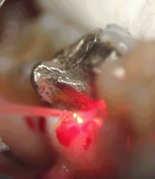

Surgery with Laser since the prosthetic edge

At this treatment and setting, one work with Anestesie. The anaemic working, allow us a very good view to be able to prepare a perfect tooth stump.